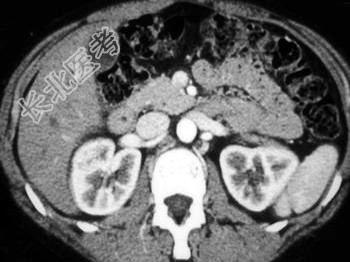

- 单项选择题根据图像,该病例最不可能的诊断为 ( )

A、嗜酸细胞瘤

B、单纯性囊肿

C、肾细胞癌

D、转移

E、以上都不是